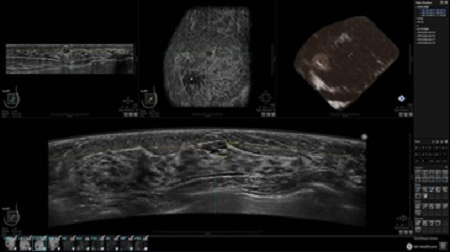

• Получение объемных 3D изображений с возможностью покадрового просмотра

• Получение изображений в поперечной плоскости (в реальном времени) и в коронарной плоскости (статическая, для указания нахождения соска)

• Отображение объемных 3D ультразвуковых изображений, которые состоят из традиционных поперечных и воссозданных коронарных и сагиттальных проекций

• Возможность отображения полного 3D изображения

• Стандартизованная ориентация изображения: «толстый срез» в коронарной плоскости; поперечная; сагиттальная плоскость; радиальный и антирадиальный поворот изображения; просмотр исключительно области интереса

• Изменяемая толщина среза: 0,5 - 10,0 мм (шаг 0,5 мм)

• Срез: 0,5 - 2,0 мм (шаг 0,5 мм)

• 360 ° APC - отображение области по «любой точке компаса»

• Одновременный просмотр двух изображений для сопоставления в коронарной плоскости